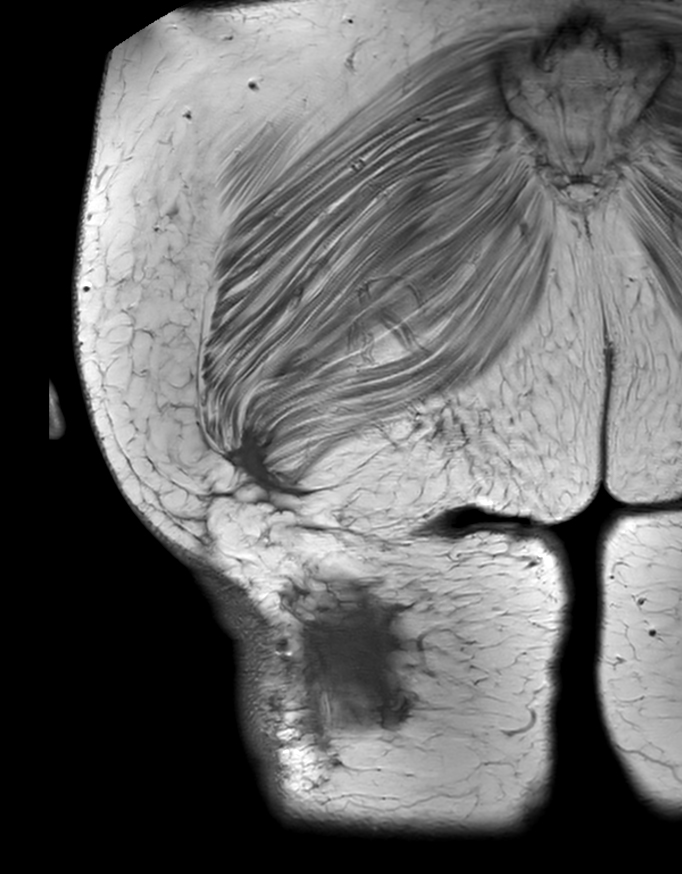

mDIXON MRA (MIP) - Upper leg